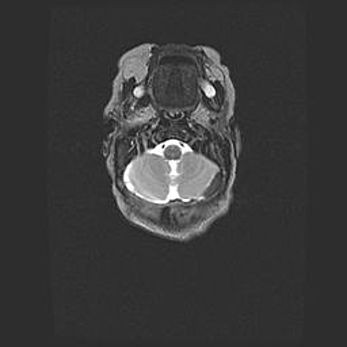

Церебральная ишемия II.

Возраст: 5 дней

Вес: 3400 г

Пол: женский

Окружность головы: 35 см

Срок гестации: 39 недель

Церебральная ишемия – это заболевание, характеризующееся недостаточностью (гипоксией) либо полным прекращением (аноксией) снабжения мозга кислородом по причине закупорки одного или нескольких сосудов. Это приводит к  что метаболическим расстройствам различной степени тяжести в тканях головного мозга, развитию коагуляционных некрозов и гибели нейронов.